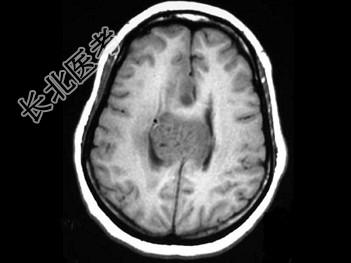

- 单项选择题女,31岁, 癫痫发作,头痛, 头晕,结合图像, 最可能的诊断是 ( )

A、脑膜瘤

B、脑囊肿

C、星形细胞瘤

D、脑膜炎

E、室管膜瘤